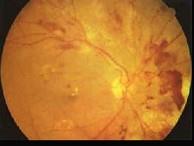

问题 糖尿病眼部病变中导致失明的主要原因是() {图1} {图2} {图3}

选项 A.白内障 B.微血管瘤 C.硬性渗出 D.视网膜小静脉扩张 E.增殖性视网膜病变

答案 E